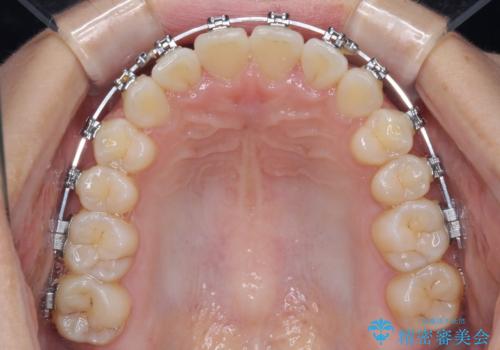

- 矯正装置

- メタルブラケット

- 上下前歯のデコボコを気にして来院された患者様です。

ワイヤー矯正でもインビザラインでも、どの装置でも対応可能でしたが、安価で楽して素早く治療を終えたいとのことで、メタルブラケット装置による矯正治療を行うこととしました。

治療中は大きなトラブルもなく、予定の1年半でスムーズに治療を終えることができました。